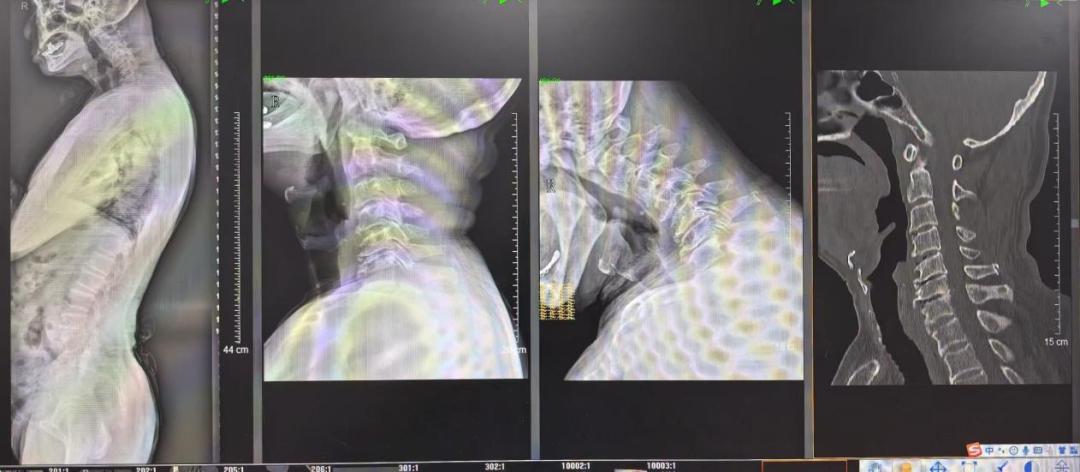

术前影像

常年无法正常抬头的老张在生活中备受折磨、苦不堪言,家里人也埋怨他习惯不好,认为是常年低头玩手机导致的,多次求医未果。就这样,老张的病情逐年加重,后背的“富贵包”也越来越大,近2个月以来,连每天三餐饭都无法抬头完成,且开始出现吞咽和饮水困难,严重影响日常生活。在小孩和老伴的陪同下,老张来到南方医科大学第三附属医院(简称“南医三院”)骨科就诊。骨科专家金大地教授接诊患者,门诊拍片提示老张多节段颈椎间盘严重退变、椎间关节失稳,颈椎严重后凸畸形,建议张先生住院治疗。

老张入院后,南医三院脊柱外科一科主任医师黄敏军组织多学科会诊,医生们凭借丰富的临床经验和敏锐的洞察力,通过系统的体格检查结合基因检测技术和肌电图等多项检查,结合多学科会诊意见,排除运动神经元疾病、神经肌肉接头疾病、风湿性疾病及内分泌代谢性疾病等,最终确诊老张为罕见的颈椎退行性疾病“垂头综合征”(Dropped-head Sydrome)。